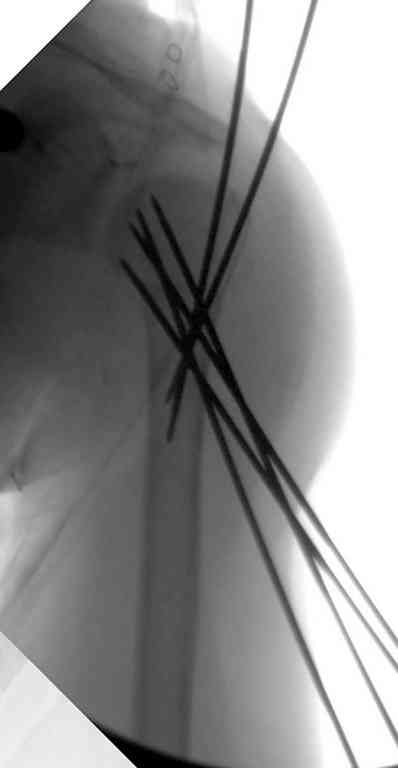

Неплохой бюджетный и косметический вариант, хотя в руках автора это это очень просто, а у нас приходилось "посветиться ", репозицию проводили

короткими 2 мм спицами -джойстиками,их же использовали для временной фиксации (а в некоторых случаях и для окончательной), варинат фиксация

TENами.

Неправильно выбранная тактика по фиксации или технические ошибки во время операции могут привести к серьезным осложнениям. Здесь привожу

пример из нашей практики, вроде обычный перелом шейки, фиксированный популярным методом "Сиэтла" - множественными спицами 2.8 мм с резьбой на конце.

При первичном осмотре в поликлинике через 3 недели обнаружили миграцию двух спиц, срочно госпитализированному на второй день перед операцией на всякий случай сделали снимок, одна спица находилась под ключицей в шейном отделе (на снимке).